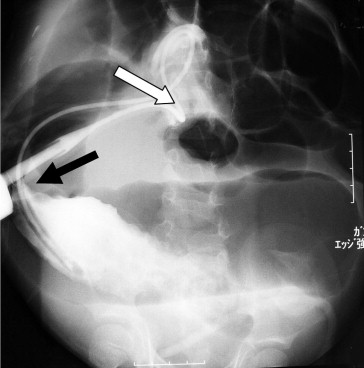

A 5-year-old female was admitted to our institution due to a marked abdominal distention and frequent vomiting. She had previously been diagnosed with prune belly syndrome with multiple congenital anomalies, including atresia ani, during the neonatal period. A transverse loop colostomy and cystotomy had been performed due to the atresia ani during the neonatal period. Mental retardation had also been diagnosed. An abdominal plain X-ray film showed a markedly distended intestine. A Nelaton catheter was inserted from the colostomy into the dilated intestine under fluoroscopic imaging, and a large amount of gas blew out through the tube, resulting in temporary improvement of her symptoms. However, her abdomen gradually became distended again later. A contrast study through the stoma showed a bird’s beak sign-like finding in the site proximal to the colostomy (Fig. 1), and the contrast CT scan revealed the whirl sign at the right upper abdomen near the colostomy (Fig. 2). An emergency laparotomy was performed because the CT scan findings suggested the presence of the volvulus, and the symptoms were recurrent in spite of deflation by means of a catheter. The surgical findings showed a nonrotation type of malrotation and that the total colon therefore was not fixed to the retroperitoneum. A volvulus of the colon existed, with ischemic changes at the site proximal to the colostomy. The dilation of the colon in the site proximal to the colostomy was also noticed. The release of the colonic volvulus led to the improvement of its ischemia. Therefore, a resection of the colon was not performed. The previous loop colostomy was divided into proximal site and distal site. The proximal site of the previous colostomy was fixed to the abdominal wall as a new end colostomy, while the distal site of the previous colostomy was completely closed. The patient’s postoperative course was uneventful, and she was discharged on the 16th day after the operation. During the 2-year follow-up period, no further symptoms of volvulus have been observed.

The contrast enema image demonstrates a tapering of the contrast column (black ...

Figure 1.

The contrast enema image demonstrates a tapering of the contrast column (black arrow), which resembles a “bird’s beak sign.” The white arrow shows the position of the colostomy.